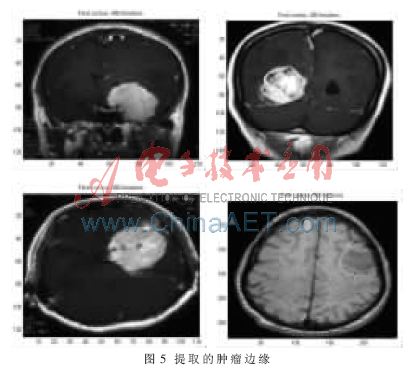

根据初始轮廓模型,应用改进主动轮廓模型提取脑部肿瘤边缘。图4为一组勾画了脑部肿瘤初始轮廓的MR图像,图5为在图4的初始轮廓下,基于改进主动轮廓模型提取的肿瘤边缘。从图5可以看出,基于改进主动轮廓模型提取脑部肿瘤边缘不仅能够接近真实边缘的凹陷处,而且快速收敛到物体的真实边缘。实验结果证明,主动轮廓模型中改进的一阶连续性能量是有效的,使初始轮廓能够接近物体凹部,同时很好地保持了个点之间的连续性,改变了原始主动轮廓模型的非凸性性质。由于增加了自适应改变大小的外部约束力来增大外能的吸引范围,因此主动轮廓模型不依赖初始位置的选取。

传统的主动轮廓模型虽然应用广泛,但是它却有两个缺点:(1)由于图像能定义为基于图像梯度的势能,图像力的吸引范围局限在图像边缘附近,在初始模型与真实模型的对象边缘相差较大时,模型可能收敛到局部极小值而不能趋向真实的边缘;(2)不具有非凸性,不能接近边缘的凹陷处。本文提出的改进主动轮廓模型在提取MRI图像边缘时,不仅能够接近真实边缘的凹陷处,还能够快速收敛到物体的真实边缘。实验结果不仅证明了主动轮廓模型中改进的一阶连续性能量是有效的,而且证明了增加自适应改变大小的外部约束力能够增大外能的吸引范围,使主动轮廓模型不依赖初始位置的选取。